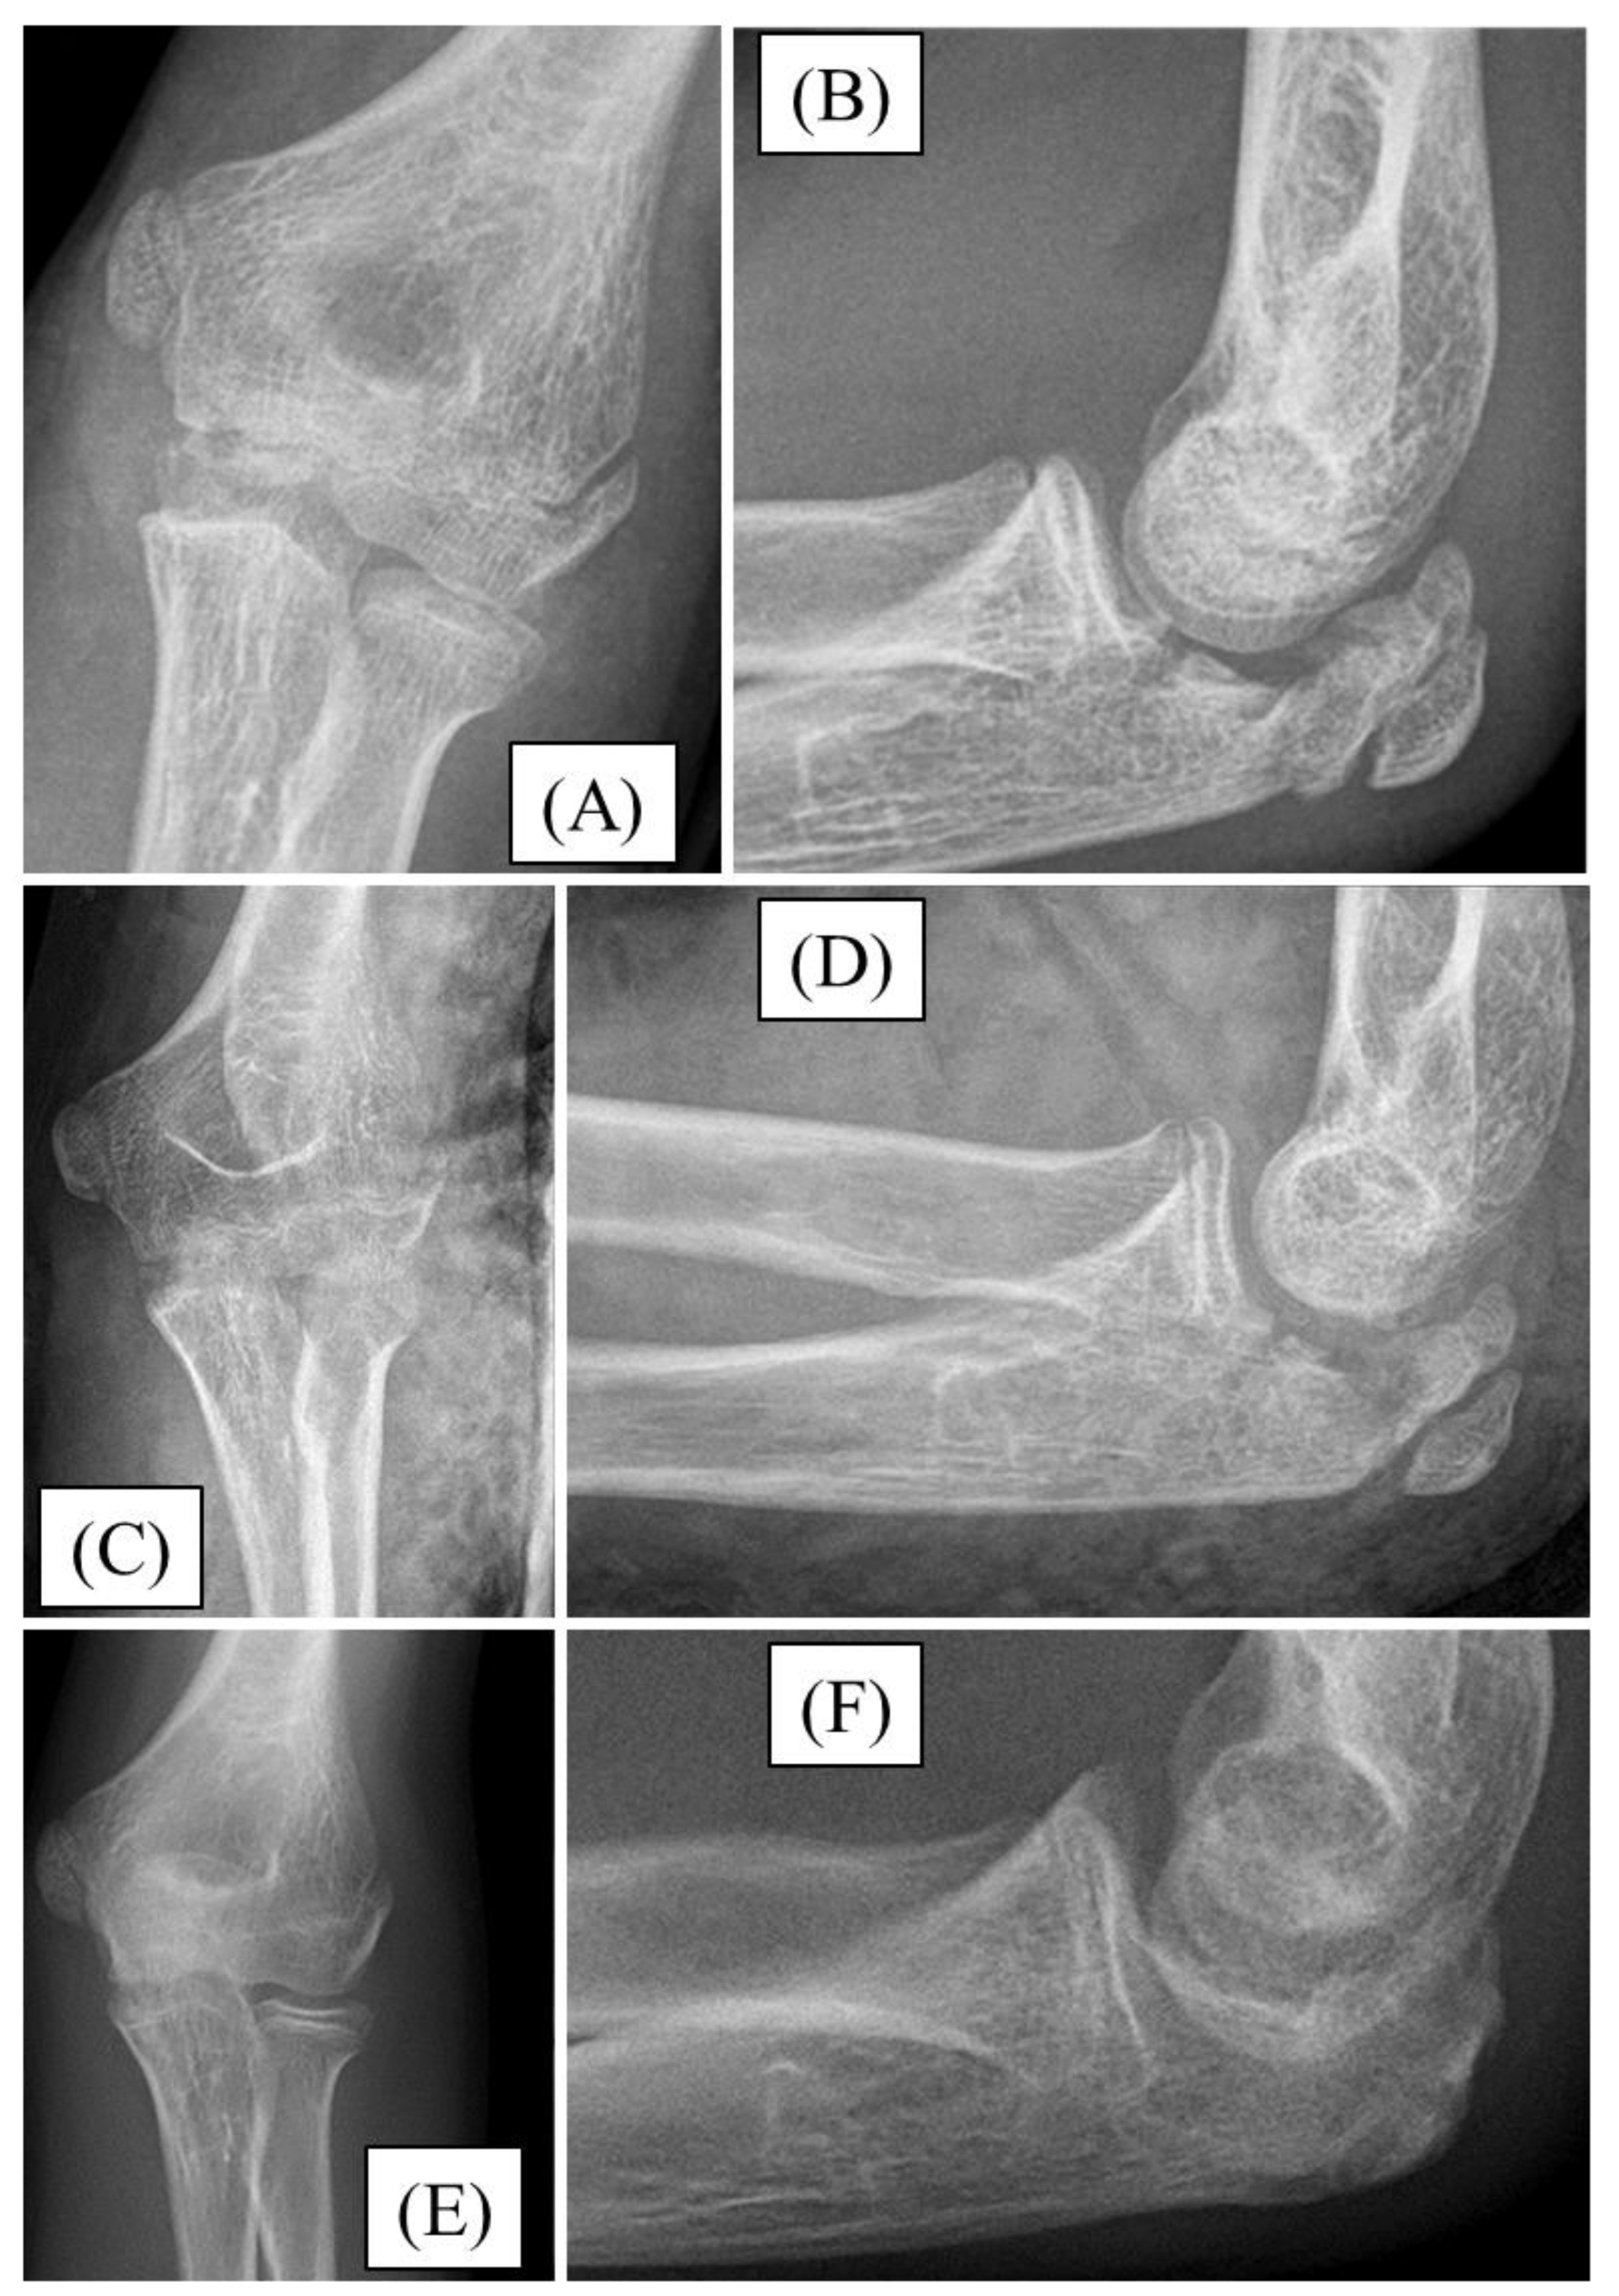

3.2. Case 2

After falling down the stairs, a 12-year-old boy sustained an injury. Significant swelling and restricted joint movement developed above his left elbow. A Mayo type II/B olecranon fracture with joint step formation was confirmed by X-rays (Figure 3A,B). After preparation, the fracture was reduced and stabilized with absorbable PLGA pins and a PDS loop. The follow-up X-ray showed the fracture in good alignment (Figure 3C,D). The postoperative period was uneventful. For three weeks, the left upper limb was restrained in a long arm cast. Following the restriction, the child received active physiotherapy. All through the follow-up, we observed the gradual mending of the fracture. One-year follow-up radiographs confirmed finished fracture healing, with full elbow joint function (Figure 3E,F).

Figure 3. Preoperative X-rays from AP (A) and lateral (B) aspects of olecranon fracture. Postoperative X-rays show good reduction and perfect articular congruency AP (C) and lateral (D). One year later, the fracture was entirely healed with no sign of articular incongruency (E-F).